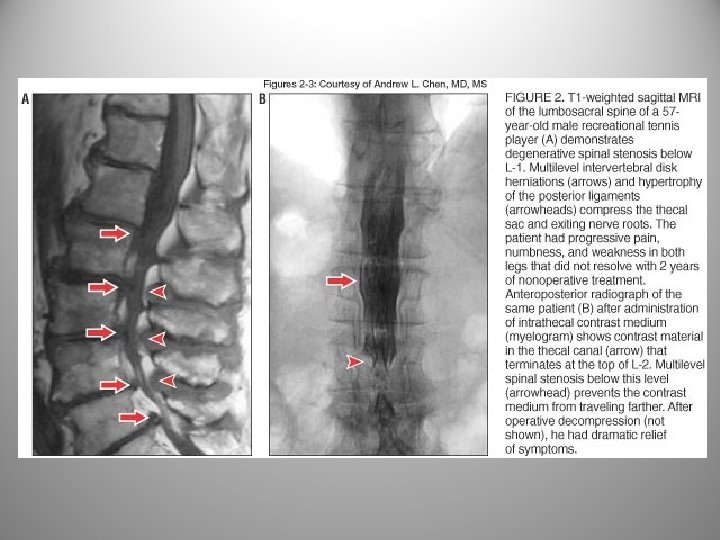

Diagnostics: Myelogram n n n Test use: To identify anatomical abnormalities within the spinal canal. Procedure: A radio-opaque dye is placed into the dural sac and a CT scan of the area is then performed. Results: The CT scan is then read to identify whether any filling defects are seen within the spinal cord and the nerve roots. Defects may represent, a herniated disc, bone spurs, infections, malignancies, etc.

MRI